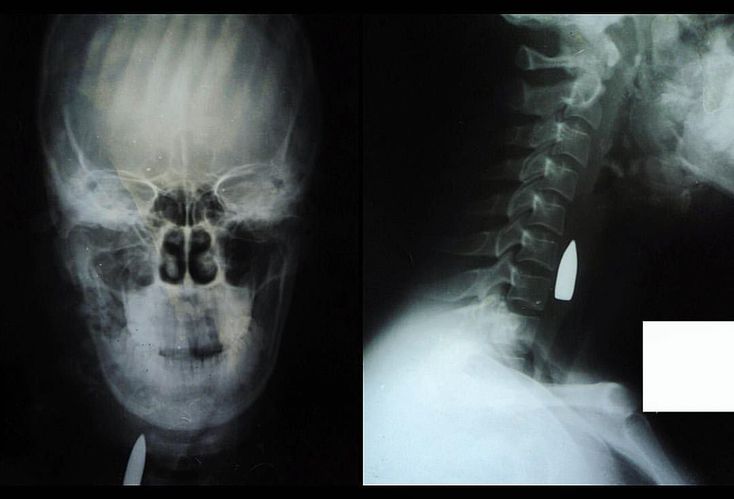

How would you start treating? These head and neck radiographs depict an atypical, accidental AK-47 rifle injury to the right side of the face and neck. The anteroposterior view on the left shows the bullet in the right side of the neck, as well as a comminuted fracture of the mandible (angle and ramus) and maxillary antrum. The lateral radiograph on the right also reveals the bullet lodged in the neck, anterior to the bodies of the cervical vertebrae 6 and 7. Gunshot wounds to the neck are highly likely to cause significant injury. Previously, injuries that violated the platysma muscle were though to require surgical neck exploration; however, because a large number of these neck explorations were ‘’negative’’, advanced imaging in stable patients prior to surgical exploration appears to be a reasonable approach. Cervical spine immobilization is not typically recommended in penetrating neck trauma. However, high-force mechanisms, such as a gunshot wound, make cervical spine injury more likely. Therefore, clinicians should consider immobilizing the cervical spine.